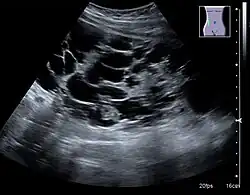

The hydronephrosis is typically graded visually and can be divided into five categories going from a slight expansion of the renal pelvis to end-stage hydronephrosis with cortical thinning (Figure 15). The evaluation of hydronephrosis can also include measures of calyces at the level of the neck in the longitudinal scan plane, of the dilated renal pelvis in the transverse scan plane and the cortical thickness, as explained previously (Figure 16 and Figure 17).[1]

Figure 16. Hydronephrosis with dilated anechoic pelvis and calyces, along with cortical atrophy. The width of a calyx is measured on the US image in the longitudinal scan plane, and illustrated by '+' and a dashed line.[1] -

Figure 17. Same patient as in Figure 16 with measurement of the pelvis dilation in the transverse scan plane illustrated on the US image with '+' and a dashed line.[1]